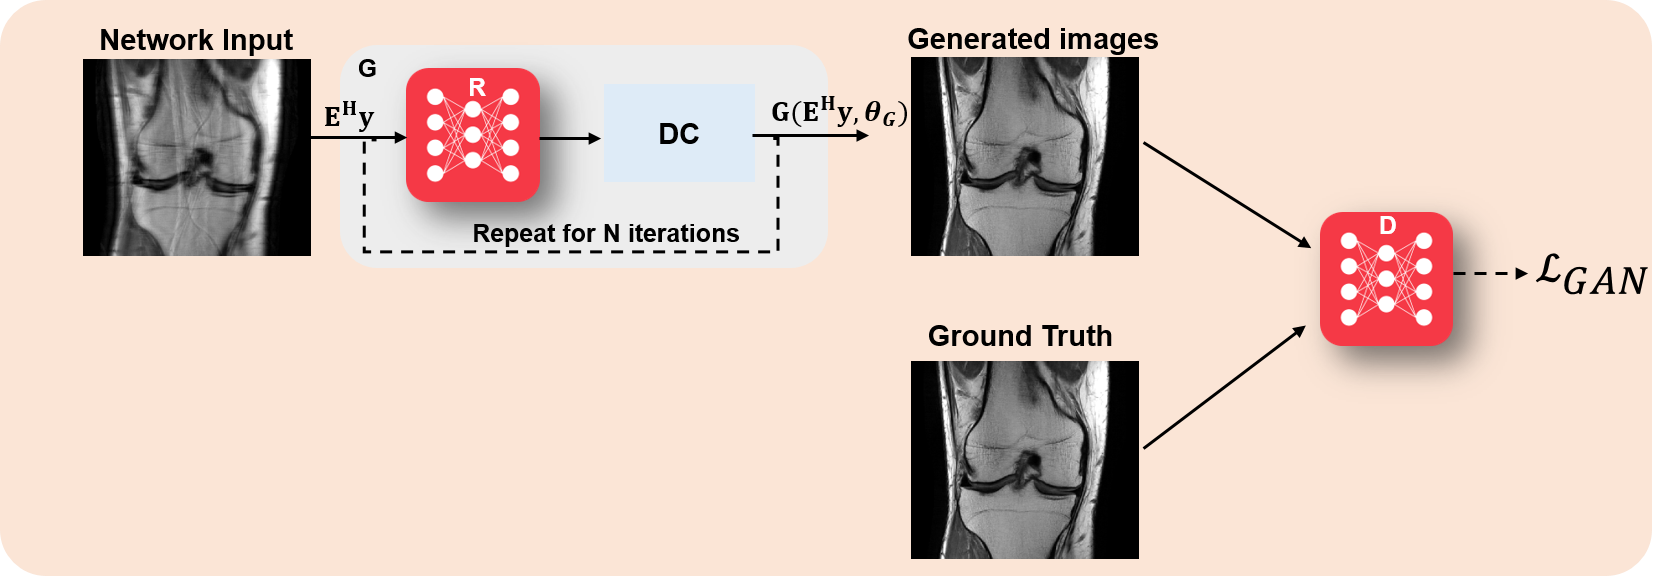

The idea of using GANs in computational MRI was first proposed in [38]. In this case, the generator network used the zero-filled images as input instead of a random distribution, leading to the loss function

| (15) |

At inference time, the generator was used to produce the desired output. Here was an image enhancement network, followed by a data consistency step, for instance implemented by a gradient descent step as in Eq. (8a); while the discriminator was essentially used to implement an adversarial loss term to improve the recovery of finer details. Thus, this formulation used supervised training with paired data. A high-level overview of this approach is shown in Figure 2. A more recent work replaced this generator with a variational autoencoder based generator that also allowed for uncertainty quantification [39].